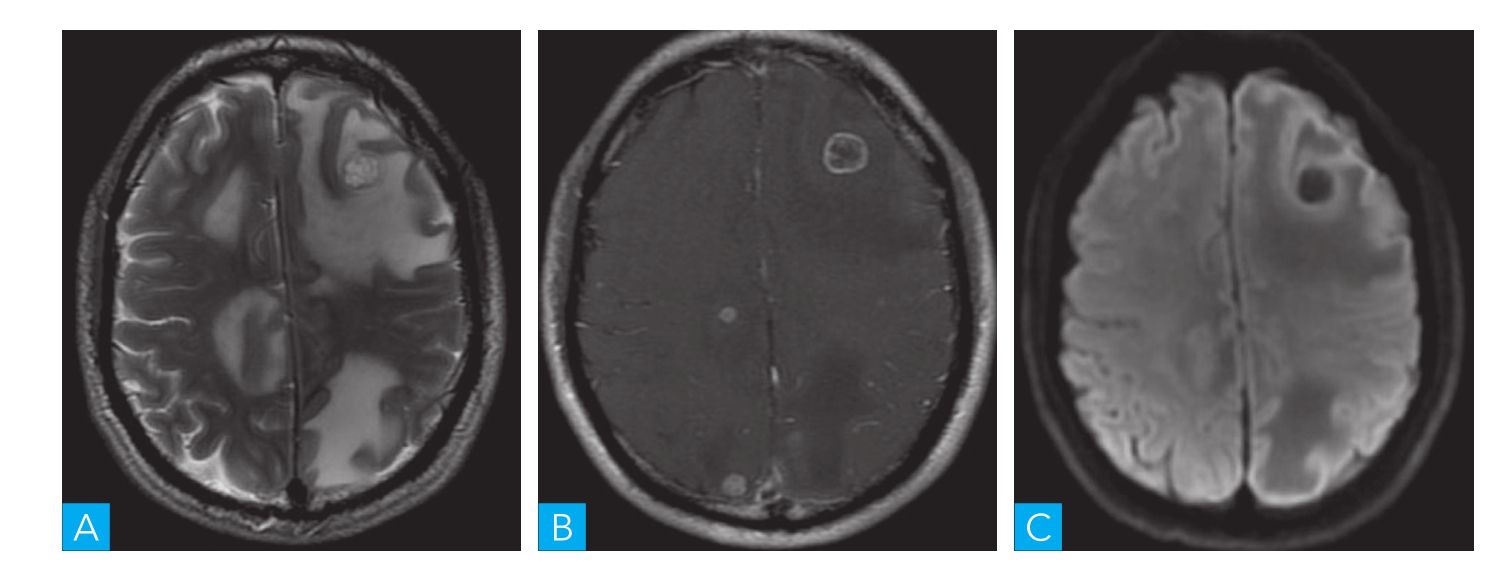

图1-4-2 原发中枢神经系统淋巴瘤MRI扫描

A.轴位T2-FLAIR;B.轴位T1WI增强;C.轴位DWI

是一种侵袭性非常高的非霍奇金淋巴瘤,进展迅速。临床上表现为局灶性神经系统损害、颅内压增高、癫痫等。CT及MRI上肿瘤多累及幕上近中线部位的脑白质,额叶、胼胝体、丘脑、基底节区及深部脑室周围结构是其好发部位。肿瘤的密度和信号与脑灰质相似,由于肿瘤细胞成分多,间质少,含水量相对少,核浆比高,故T2WI信号一般不高,DWI信号显著增高,肿瘤因为破坏血脑屏障而发生明显的强化,但肿瘤本身无明显血供,新生血管少,故灌注成像显示肿瘤呈低灌注,与胶质母细胞瘤的高灌注明显不同(图1-4-2)。